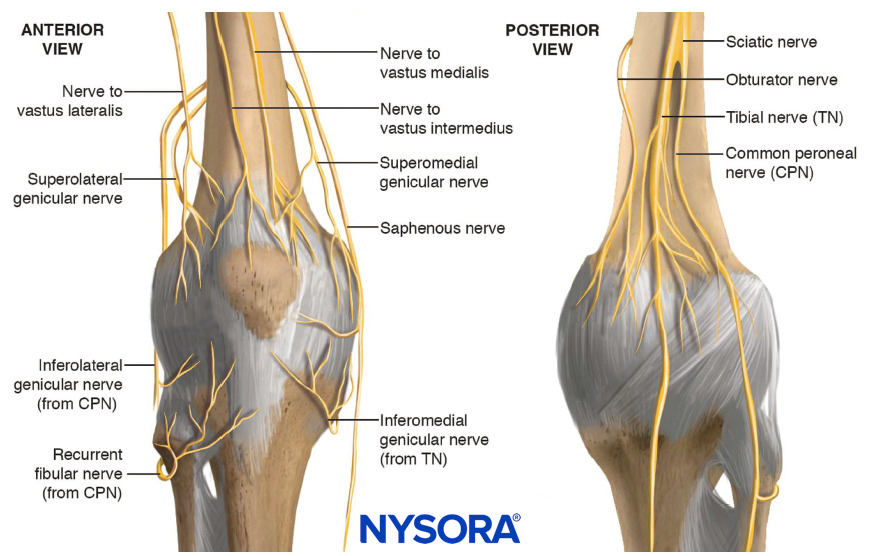

The innervation of the knee is complex, with branches originating from femoral, obturator, and sciatic nerves (Figure 1). The interindividual variability explains the discrepancy in the literature over the nomenclature and the origin of the genicular nerves.

FIGURE 1. Innervation of the knee. The origin of the superomedial and superolateral genicular nerves (from the sciatic nerve or from the femoral nerve) is controversial.

To facilitate understanding of knee innervation, most authors divide the knee into an anterior and posterior compartment, and then further divide the anterior compartment into four quadrants. For the purpose of the technique description, the genicular nerves are called the superolateral (SLGN), superomedial (SMGN), inferolateral (ILGN), and inferomedial (IMGN) genicular nerves, which innervate primarily each corresponding quadrant. Several cadaver studies also show a contribution from other branches such as the recurrent peroneal nerve, the nerve to the vastus medialis, intermediate, lateralis, and the infrapatellar branch.

- The SLGN courses around the femur shaft to pass between the vastus lateralis and the lateral epicondyle. It accompanies the superior lateral genicular artery.

- The SMGN courses around the femur shaft, following the superior medial genicular artery, to pass between the adductor magnus tendon and the medial epicondyle below the vastus medialis.

- The ILGN courses around the tibial lateral epicondyle deep to the lateral collateral ligament, following the inferior lateral genicular artery, superior of the fibula head.

- The IMGN courses horizontally below the medial collateral ligament between the tibial medial epicondyle and the insertion of the collateral ligament. It accompanies the inferior medial genicular artery.

- The recurrent peroneal nerve originates in the inferior popliteal region from the common peroneal nerve and courses horizontally around the fibula to pass just inferior of the fibula head and travel superior to the anterolateral tibial epicondyle. It accompanies the recurrent tibial artery.